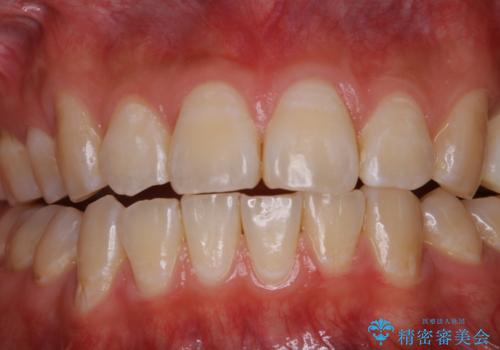

紅茶による着色を1日できれいに

- 紅茶を頻繁に飲むため、歯の黄ばみが気になるとのことでした。PMTC60分コースを行いました。

PMTC(保険外治療)は、毎日の歯磨きで落としきれない汚れや、コーヒ、紅茶・タバコのヤニなどの着色も除去します。目には見えない歯と歯の間・歯肉の境目などに残っているプラーク(歯垢)もしっかり取り除きます。PMTCでは専門的な機械や材料を使用して、徹底的に汚れを除去するため、虫歯・歯周病・口臭予防などにつながります。

また、仕上げのトリートメントでは歯の表面の凸凹にミネラルを補給して、ツルツルの表面に仕上げます。定期的にPMTCを行うことにより、歯質の強化になり着色がつきにくい状態になります。